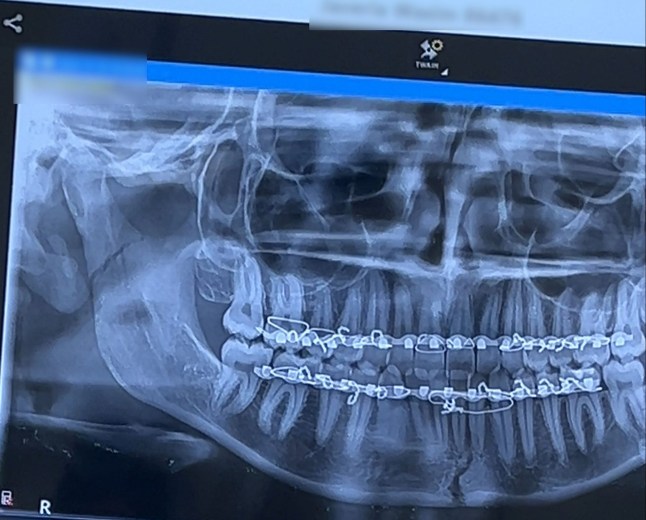

The duo called an ambulance to take Javeria to the hospital, where an X-ray and CT scan found she suffered two fractures in her jaw.

After the one-hour procedure, her jaw was put back into place and a bar was inserted on her top and bottom gums, wiring it shut for the next six weeks.

![PIC FROM KENNEDY NEWS AND MEDIA (PICTURED: JAVERIA'S X-RAY REVEALED TWO FRACTURES IN HER JAW) A student was horrified when a 'jawbreaker' candy lived up to its name as she tried the 'dumb idea' of biting through it??? snapping her jaw in two places. Javeria Wasim and her friend decided to get 'giant' three-inch diameter jawbreakers while out shopping last month [19 November]. Once back at her university dorm room, the 19-year-old admits she became impatient to get to the gumball in the centre and tried to bite into the candy rather than licking her way through the treat. DISCLAIMER: While Kennedy News and Media uses its best endeavours to establish the copyright and authenticity of all pictures supplied, it accepts no liability for any damage, loss or legal action caused by the use of images supplied and the publication of images is solely at your discretion. SEE KENNEDY NEWS COPY - 0161 697 4266](https://latinnudists.com/wp-content/uploads/2024/12/SEI_234169759-0abe-e1735071127299.jpg)